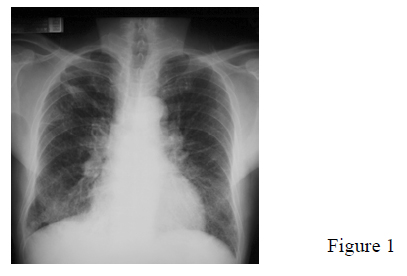

In mid 2004, he started to have productive cough with mucoid sputum. He also had mild exertional dyspnoea but no haemoptysis or chest pain. Constitutional symptoms were also absent. CXR showed new BLZ fine reticulonodular shadows (Fig.1). Sputum examination for AFB, cytology and pyogenic organisms were all negative.